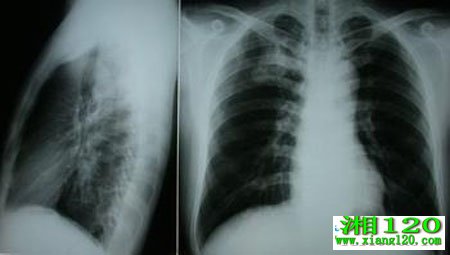

你要当心肺癌来袭

肺癌发生于支气管粘膜上皮,亦称支气管癌。近50年来许多国家都报道肺癌的发病率明显增高。肺癌不容小觑,如果您或您周围的朋友有以下的情况,那可就要注意了。